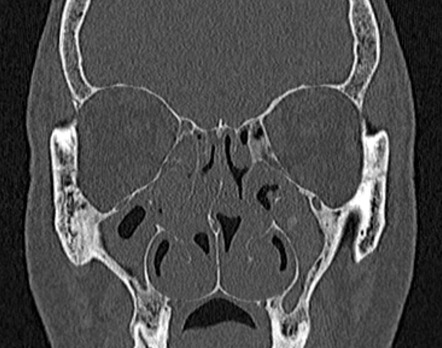

CT (kompjuterizirana tomografija)

U slučajevima kada su potrebne dodatne informacije, CT nosa i sinusa pruža trodimenzionalni prikaz unutrašnjih struktura. Pomaže u otkrivanju:

Precizne lokacije devijacije septuma.

Prisutnosti polipa, cista ili upalnih promjena.